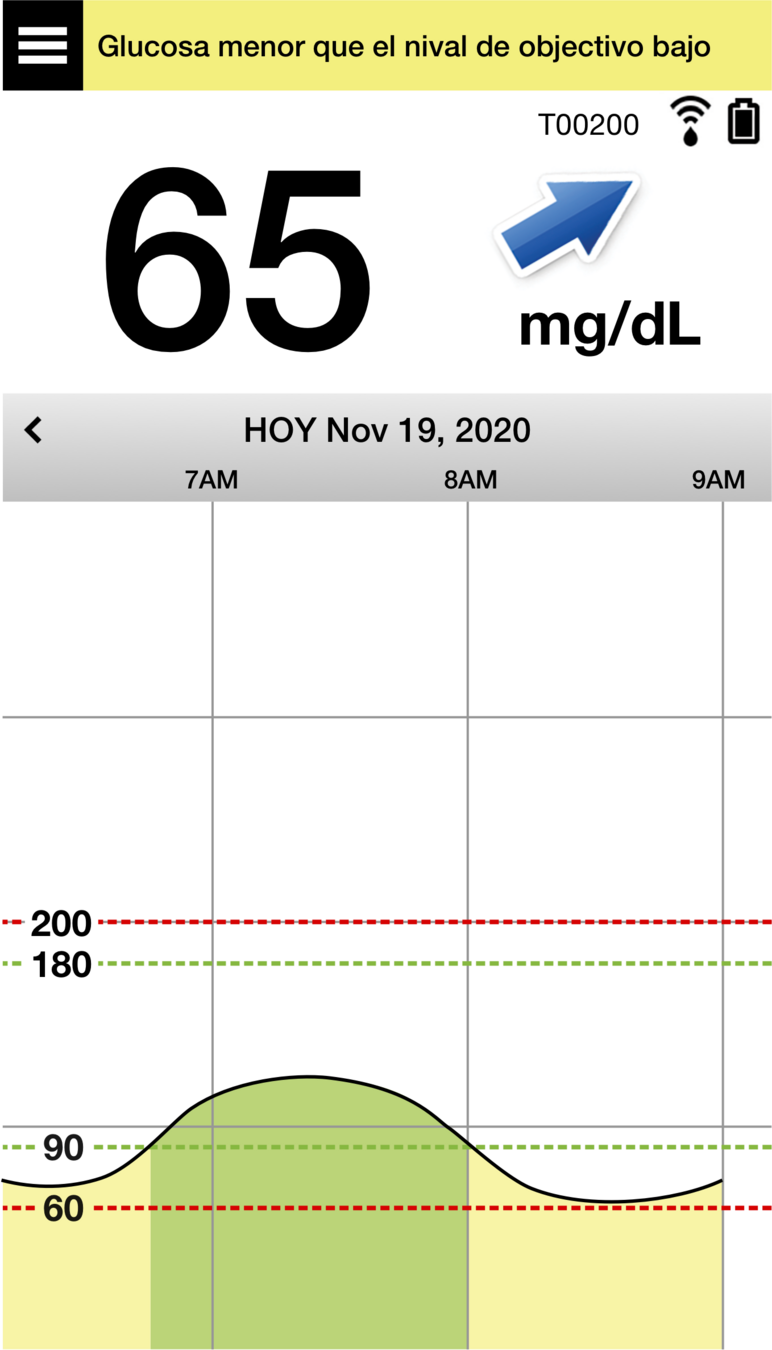

Y, en la parte inferior, se encuentra el gráfico de tendencia de la glucosa.

Las líneas discontinuas rojas indican los niveles de alerta de glucosa alta y baja, y las líneas discontinuas verdes indican el intervalo objetivo.

Todos los eventos que introduzca en la aplicación (como una calibración, comida, ejercicio

o insulina) o las alertas que reciba, se mostrarán en el gráfico de tendencia con un icono.

La flecha de tendencia es una ventaja especialmente importante de la MCG.

Le permite anticiparse a su nivel de glucosa futuro y adaptar de forma preventiva sus decisiones sobre el tratamiento de la diabetes según sea necesario.

Los distintos ángulos de la flecha hacen referencia a una velocidad de cambio distinta, como se muestra en el gráfico de la derecha:

- estable;

- aumentando moderadamente;

- descendiendo moderadamente;

- aumentando con mucha rapidez;

- y descendiendo con mucha rapidez.

Niveles de glucosa que aumentan o descienden gradualmente, a una velocidad de entre 0,00 mg/dL

y 1,0 mg/dL por minuto.

Niveles de glucosa que aumentan moderadamente, a una velocidad de entre 1,0 mg/dL y 2,0 mg/dL por minuto.

Niveles de glucosa que descienden moderadamente, a una velocidad de entre 1,0 mg/dL y 2,0 mg/dL por minuto.

Niveles de glucosa que aumentan con mucha rapidez, a una velocidad superior a 2,0 mg/dL por minuto.

Niveles de glucosa que descienden con mucha rapidez, a una velocidad superior a 2,0 mg/dL por minuto.